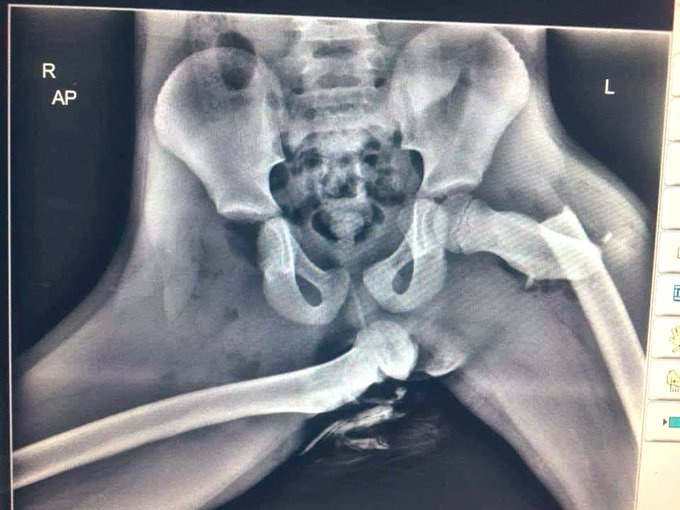

Ilyenkor súlyos sérülések keletkezhetnek a comb izomzatában, a combcsont törhet, ahogy a medence is. Ez a kétségkívül sokkoló röntgenfelvétel figyelmeztet arra, hogy milyen sérüléseket lehet ilyenkor összeszedni. Nem kell orvosi végzettség ahhoz, hogy lássuk a súlyos sérüléseket a képen. Jobb oldali törött combcsont, medencetörés, kiugrott csípőcsont – vérfagyasztó látvány.

Ha így ülsz egy ütköző autóban, akkor oda a lábad 1